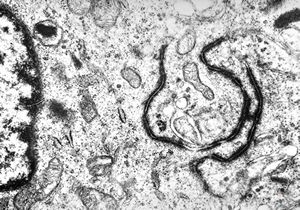

M,10y. | herpetic encephalitis